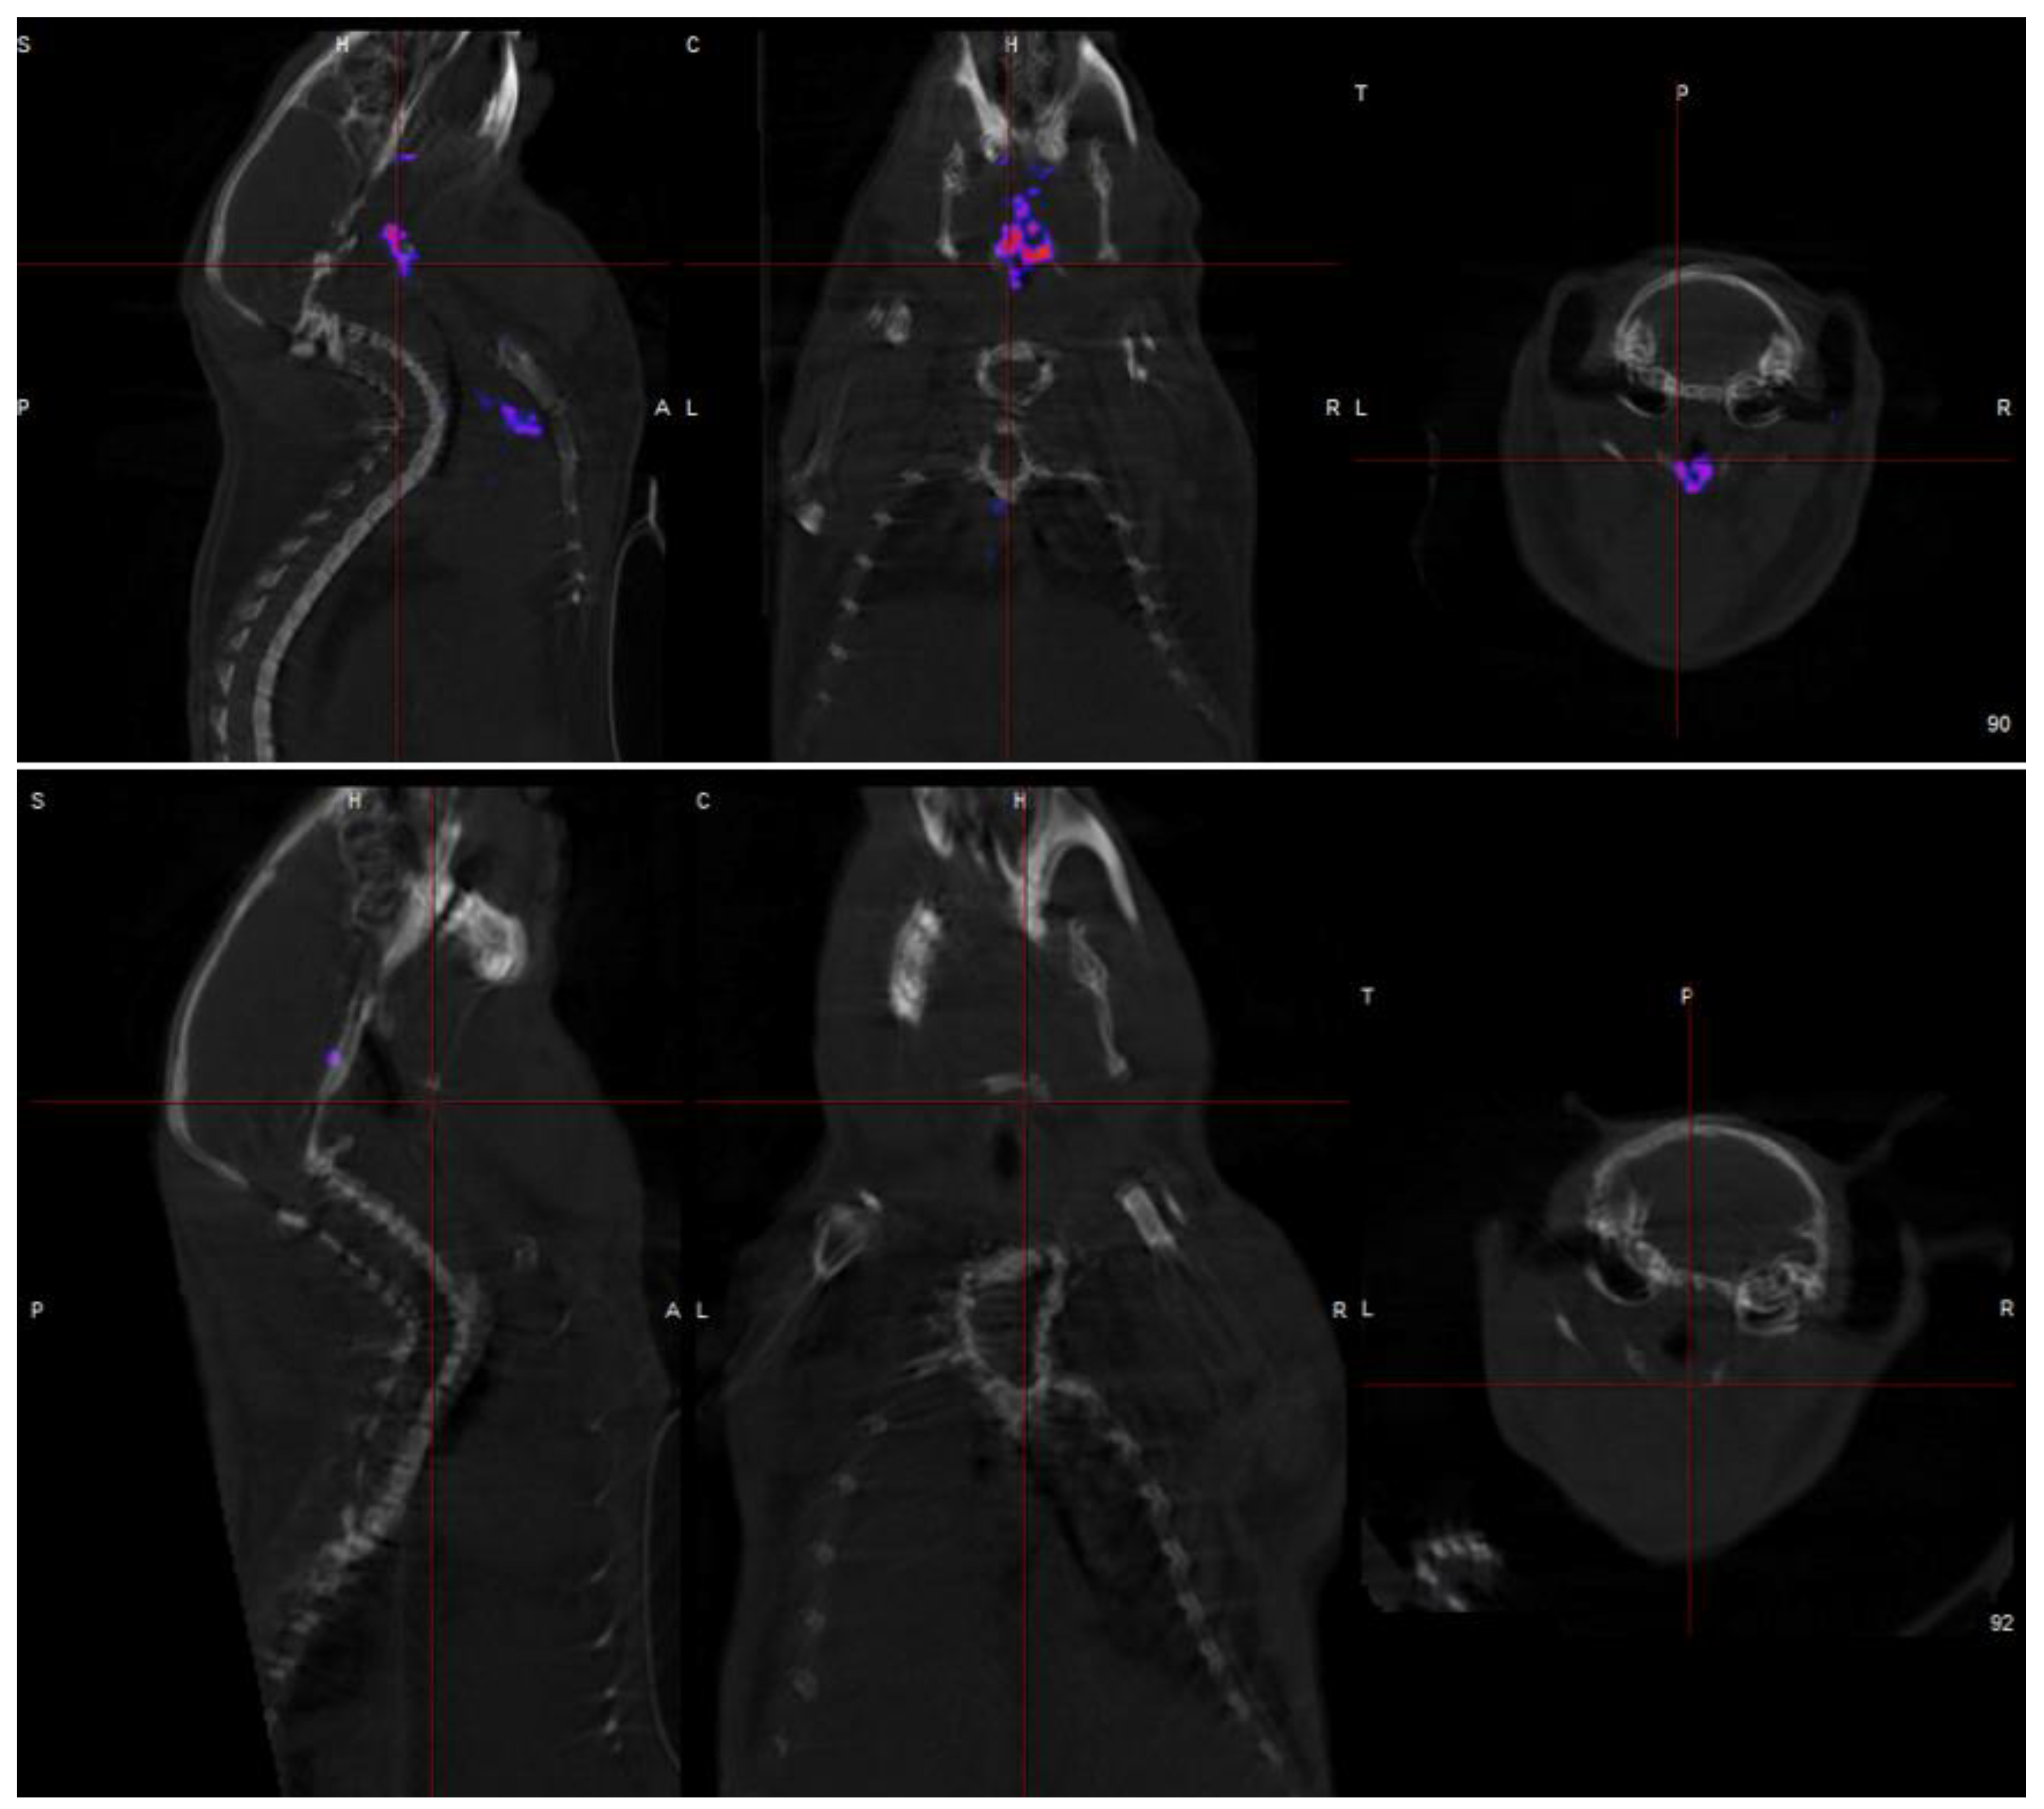

1.5. Micro-Calcifications

2. Systematic Review of 18F NaF PET in Vulnerable Plaque

2.2. Results

3. Discussion